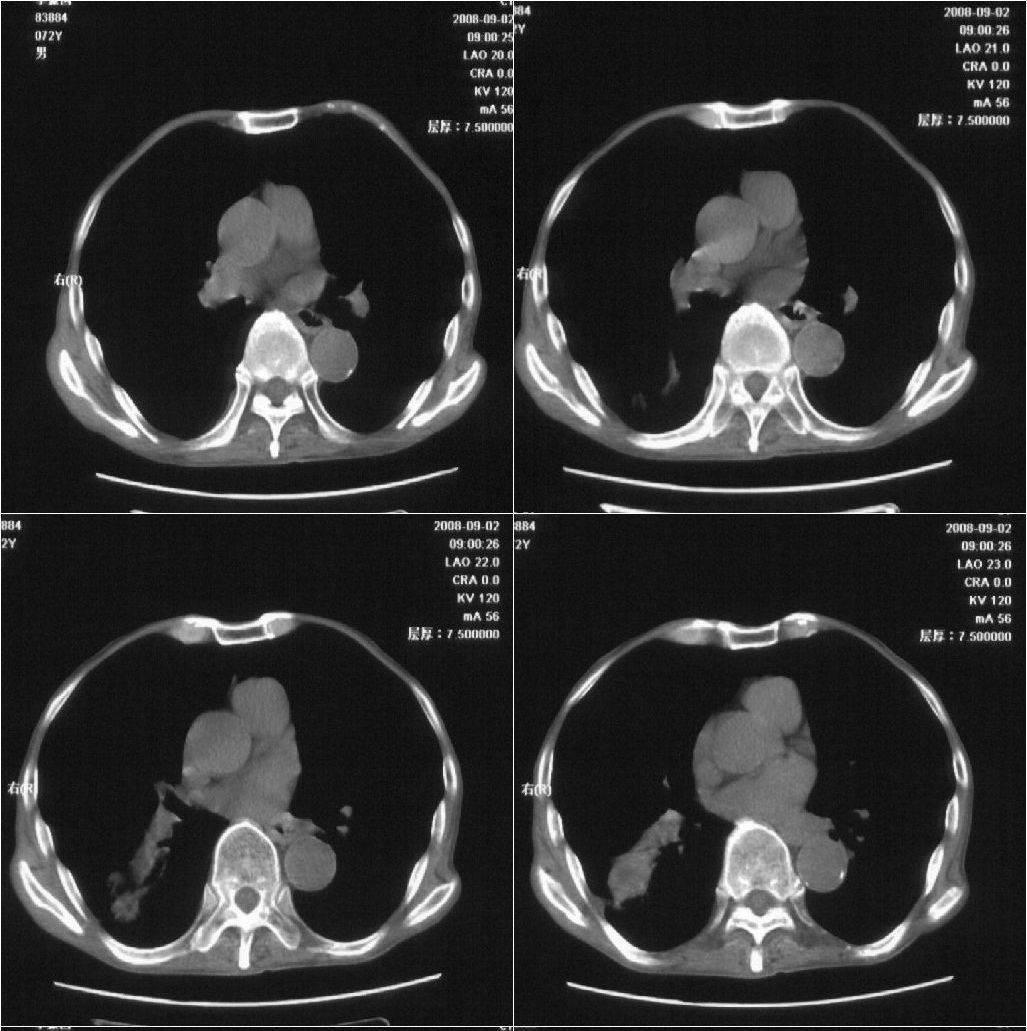

标题: CT15789:男性,72岁。食管癌术后14年。 [打印本页]

标题: CT15789:男性,72岁。食管癌术后14年。

痰培养:见葡萄球菌,霉菌少量生长。(此片系外院所作,仅提供了增强后的ct值为100hu,中心的坏死部分无强化,患者现在身体状况欠佳,为恶液质状态)

考虑肺癌可能性大伴阻塞性炎症

周围型肺癌可能性大.

考虑右肺下叶感染性病变(肺脓肿?);建议抗炎治疗后复查。

符合机遇性感染,真菌可能性大。